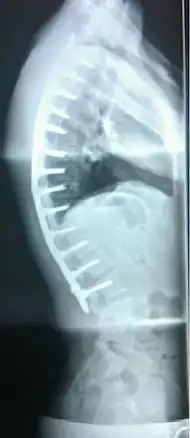

Surgery

In severe or extreme cases, patients may be treated through an extensive surgical procedure in an effort to prevent the disease from worsening or harming the body. The skeletal deformity caused by Scheuermann's disease can be corrected or partially corrected with surgical procedures, almost all of which include multi-level spinal fusion and hardware instrumentation, i.e., rods, pedicle screws, etc. It is important to realize the surgery aims to reduce pain, and not cosmetic defect. As always, surgical intervention should be used as a last resort once conservative treatment fails or the patient's health is in imminent danger as any surgical procedure is not without risk. However, the chances of complication are relatively low, and the surgeries are often successful.

There are two primary surgical techniques to correct kyphosis: posterior-only fusion and anterior/posterior fusion. While debate lingers over which surgical approach is optimal, several studies published since 2018 suggest treatment trends are favoring posterior-only fusion.[17][18][19]

The classic surgical procedure entails entering two titanium rods, each roughly 1.5 feet (0.46 m) long (depending on the size of the kyphosis) into the back on either side of the spine. Eight titanium screws and hardware are drilled through the bone to secure the rods onto either side of the spine. On the internal-facing side of the spine, ligaments (which can be too short, pulling the spine into its abnormal shape) must be surgically cut or released, not only stopping part of the cause of the kyphosis, but also allowing the titanium rods to pull the spine into a more natural position. The damaged discs between the troubled vertebrae (wedged vertebrae) are normally removed and replaced with bone grafting from the hip or other parts of the vertebrae, which once healed or "fused" will solidify. The titanium instrumentation holds everything in place during healing. The patient can expect to remain in hospital for a minimum of a week, and possibly longer. They may then be required to wear a brace for several months more to ensure the spine heals appropriately. The titanium instrumentation may stay in the body permanently, or be removed years later. Patients who have undergone such surgery may need physical therapy to manage pain and mobility. Recovery can be prolonged: typically patients are not allowed to lift anything above 5–10 pounds (2.3–4.5 kg) for 6 months to 1 year, and many are out of work for 3 to 6 months. However, once the fusion is solidified, most patients can return to their usual lifestyle within 1–2 years.